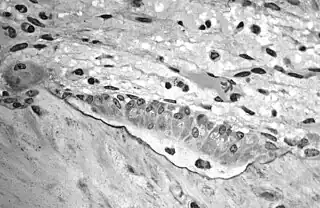

![]() A scanning electronic micrograph of bone at 10,000× magnification | |

Scanning electron microscope of bone at 100× magnification